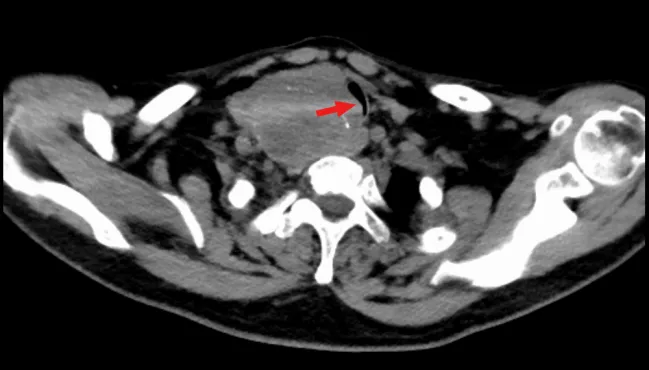

近日,王女士游玩途中,突发呼吸困难伴意识模糊,被紧急送往当地医院。为求进一步治疗,患者随即返穗,找到广州市红十字会医院肝胆胰腺甲状腺病区副主任、主任医师吴帆寻求帮助。入院后的检查结果更让人揪心,患者右侧甲状腺肿块直径超过10厘米,存在恶性可能。更严重的是,肿物向下突入胸腔,如同一只“魔手”紧紧扼住气管,导致气管最窄处仅剩4.9毫米,患者随时面临窒息风险,须尽快手术解除压迫。